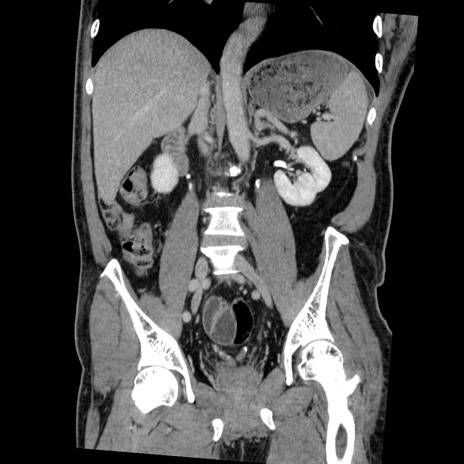

横断像

【症例】50歳代男性

【主訴】腹痛

【現病歴】AVMからの被殻出血のため回復期リハ病棟入院中。 本日午後3時頃急に下腹部痛が出現した。

【既往歴】AVM、被殻出血、虫垂炎、高血圧

【身体所見】意識晴明、左半身不全麻痺、会話の理解は良好、36.5°C、腹部:膨隆、全体に板状硬、下腹部正中に圧痛点あり、反跳痛-、筋性防御不明、右下腹部にope scar

【データ】WBC 9400、CRP 0.06